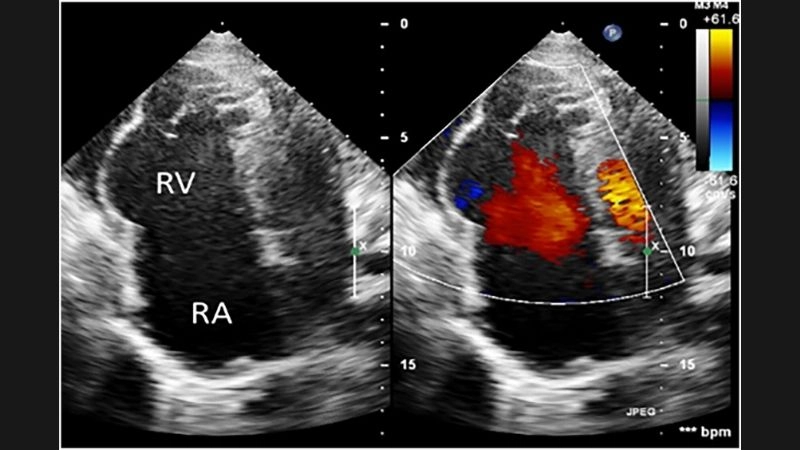

Images visual examples of Uhl's anomaly

Uhl’s anomaly is a rare congenital heart condition characterized by the near-complete absence of the right ventricular myocardium, resulting in a thin-walled and weakened heart chamber.